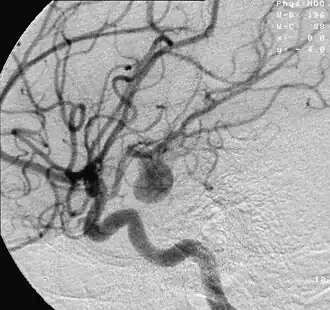

![]() Аневризма артерии головного мозга, визуализируемая посредством ангиографии | |

Окончательный диагноз ставится только на основании ангиографического исследования. Церебральная ангиография (см.) необходима также для решения вопроса о возможности хирургического лечения. При подозрении на разрыв артериальной аневризмы необходимо по возможности полное ангиографическое исследование с заполнением бассейнов внутренних сонных и позвоночных артерий. Такое исследование позволяет обнаружить множественные аневризмы и изучить особенности коллатерального кровообращения. Предпочтение следует отдать катетерпзационной методике, позволяющей за одно исследование всесторонне изучить сосуды различных сосудистых бассейнов головного мозга. Для исследования кровообращения внутренних сонных артерий с успехом может быть использована и пункционная ангиография. Для выявления артериальной аневризмы необходима серийная ангиография с наибольшим числом снимков в артериальной фазе (в течение первых одной-двух секунд). В отдельных случаях распознавание аневризм облегчается благодаря длительной задержке контрастного вещества в полости аневризмы. Ангиография позволяет также диагностировать сопутствующие разрыву аневризмы внутричерепные гематомы и выявить нарушения мозговой циркуляции, вызванные спазмом артерии.